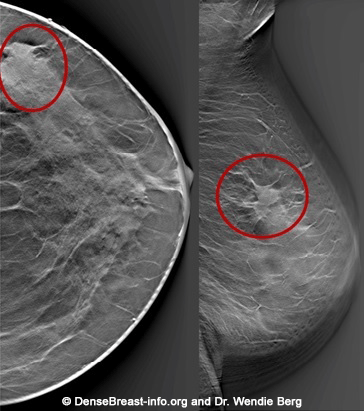

Mamografi (Altın Standart):

Mikrokalsifikasyonlar: LR (+) 15.0. (Özellikle pleomorfik/dallanan tipteyse)

Spiküle Kitle: LR (+) > 20.0.

Tanısal Kör Noktalar: Tomosentez (3D Mamografi) ve Kontrastlı Mamografi (CESM) gibi yeni nesil, LR değeri çok yüksek teknolojilerden bahsedilmeli.

İyi Prognoz İşareti: Spiküle marjlar, genellikle tümör hücrelerinin çevre dokuyla (stroma/yağ dokusu) etkileşimini ve düşük dereceli (low-grade) progresyonu gösterir. Bu durum, spiküle kitlelerin neden daha iyi bir prognoza işaret ettiğini açıklar.

Tanısal Doğrulama: Eğer bir tümör mamografide spiküle görünüyorsa ancak patolojide "HER2 pozitif" geliyorsa, bu bir uyumsuzluk (discordance) bayrağıdır; testin tekrarı düşünülebilir.